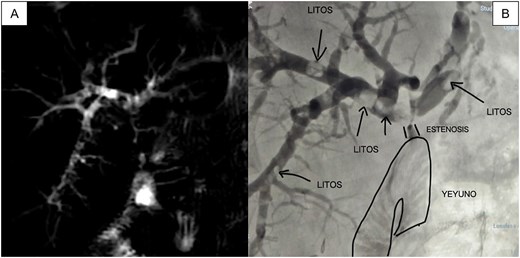

Magnetic resonance cholangiopancreatography (MRI) revealed HJA stricture without significant biliary dilation (left hepatic duct 6.2 mm, right 5.5 mm) and four intrahepatic stones (4–5 mm) (Fig. 1A). Laboratory values showed total bilirubin (TB): 3.36, direct bilirubin (DB): 3.11; aspartate aminotransferase (AST): 74, alanine aminotransferase (ALT): 63.

(A) MRI showing multiple filling defects in the right and left main branches, as well as stenosis at the level of the HJA; (B) Initial cholangiography obtained by puncturing the peripheral branch of segment VI with a 21-gauge needle confirms the same findings as the MRI.

We carried out a two–stage procedure. During the stage 1 procedure, a percutaneous transhepatic cholangiography (THPC) was performed via segment VI. Despite nondilated ducts, the duct was cannulated, and multiple filling defects (lithiasis) were observed, as well as threadlike passage of contrast toward the efferent loop (Fig. 1B). Recanalization techniques successfully traversed the stricture, and an internal-external biliary catheter (8 Fr) was placed. The procedure lasted 90 minutes, and the patient was discharged the next day without complications.